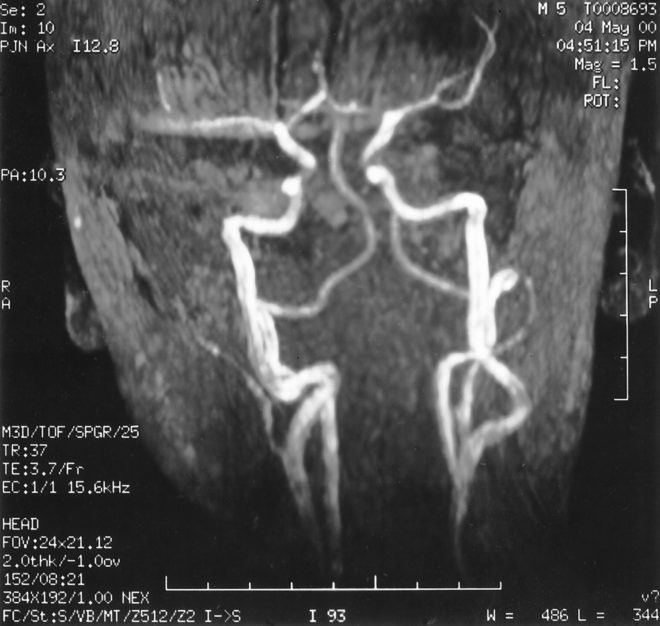

Симптомы и лечение заболеваний сонной аорты полностью соотносятся. Именно поэтому при появлении первых признаков патологии пациенту необходимо обратиться за помощью к доктору. Специалист проведет обследование больного и сбор анамнеза. Но, для того чтобы поставить диагноз, необходимо использование инструментальных методов:

- Электроэнцефалографии;

- Реоэнцефалографии;

- Компьютерной томографии.

Достаточно часто пациентам рекомендуется прохождение магнитно резонансной томографии. Информативным методом исследования является ангиография, для проведения которого вводится контраст. Пациентам рекомендовано применение ультразвукового допплерографического обследования шеи и головы.

Для постановки правильного диагноза рекомендовано проведения целого комплекса диагностических мероприятий, что позволит разработать рациональное лечение.